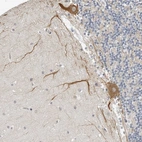

Immunohistochemical staining of human cerebellum shows moderate cytoplasmic positivity in purkinje cells.